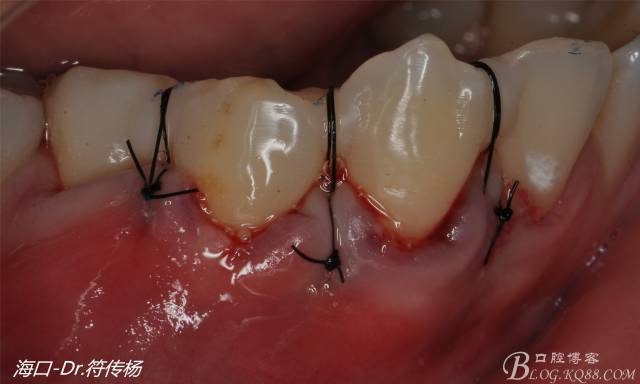

受植區(qū)建議使用雙交叉垂直懸吊縫合術(shù)來固定結(jié)締組織并能讓齦瓣更貼合根面利于術(shù)后一期愈合